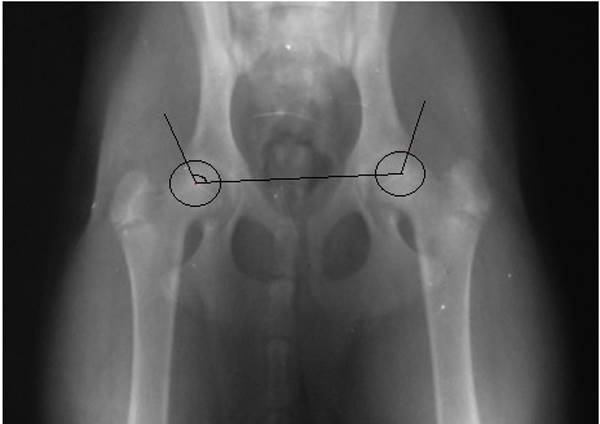

Параметров, по которым подсчитываются баллы, в классической методике 6, это система Flukiger. Каждый параметр оценивается от 0 до 5 баллов. В основе диагностики лежит определение ряда углов и соотношений в суставе, например, как на рисунке ниже:

1 параметр – угол Норберга, обозначенный на рисунке выше. Параметр оценивается в 0 баллов, если угол Норберга больше или равен 105?.